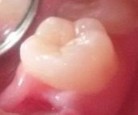

Bệnh nhân: Ng. Minh T. 9 tuổi. Răng 36, mã BA 13519/17

Sau ba tháng. ICDAS:2; Di: 22 | Sau 12 tháng. ICDAS:0; Di: 09 | Sau 18 tháng. ICDAS:0; Di: 05 |